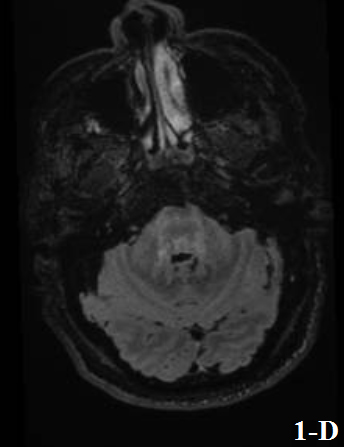

Figure 1 and Figure 2 showed the results of a brain MRI performed at admission, revealing an extensive lesion that involved the periventricular, subcortical and deep white matter.

Neuroradiological features often show an extensive compromise of the white matter with a slight mass effect at both supratentorial and infratentorial levels, in some cases spreading along the corticospinal tract and/or compromising gray matter.

Figure 1. Fluid Attenuated Inversion Recovery (FLAIR) sequence showed an extensive lesion affecting primarily the subcortical and deep white matter at frontal (a), parieto-insular and callosal (b) and temporal levels (c).

A diffuse hyperintensity was also observed at infratentorial levels, affecting primarily the midbrain (d). At the level of the right temporal epicranial soft tissue region, a lesion with heterogeneous signal and multiple dilated vascular structures were found, in relation to the patient’s prior history of congenital facial hemangioma.